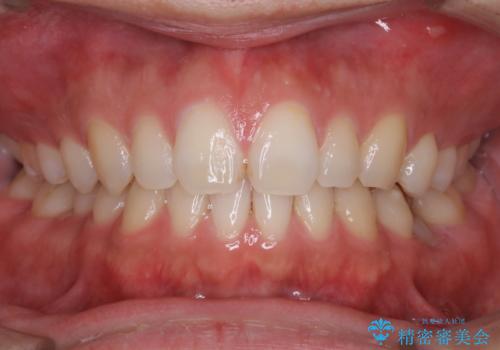

親知らずを抜いて1週間後にPMTC 歯のクリーニング

- 親知らずの抜歯後の約1週間後に抜糸(縫った部分の糸とり)で来院されました。その際、抜歯後は傷口が怖くて歯磨きが上手くできず、汚れや口臭が気になるためクリーニングも希望されました。

抜歯後は多少出血したり、違和感や痛みを感じたりすることがあります。そのため親知らずを抜いたり、外科的な処置をするといつも通りの歯磨きがしづらくなります。また、傷口の周りが心配で、歯ブラシをするのが怖くなるものです。抜歯後落ち着いたら、歯科医院にて専門の機械を使用しクリーニングをすることがおすすめです。抜歯前や後にPMTCを行うことで、お口の中の健康維持につながり、その後の感染・腫れ・口臭予防などになります。

親知らず抜歯後正常に治癒が進んでいれば1週間後から可能です。